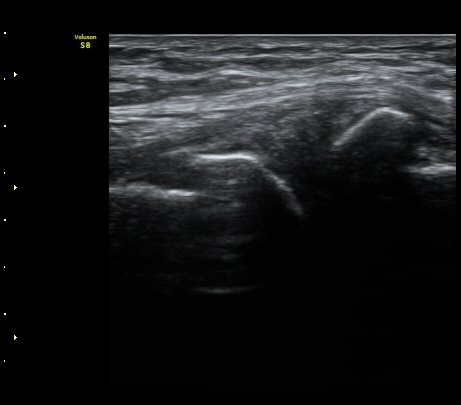

ŽÃËÀÚ¸¦ ¸»´ÜÀ¸·Î À̵¿ÇÏ´Ï º¹Àç½Å°æÀÌ ½½°³°ñÇϰ¡Áö¿Í  ºÀ°ø°¡Áö(sartorial branch)·Î

°¥¶óÁö´Â °ÍÀÌ °üÂûµÇ°í(»çÁø 3, 4, 5) µ¿¿µ»ó È­¸éÀ¸·Î º¸¸é ´õ¿í ¶Ñ·ÈÇÏ´Ù(÷ºÎ ÆÄÀÏ 1)